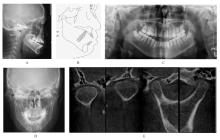

Tab.1

Cephalometric detection analysis of patient with grade Ⅲ open bite complicated with tongue hypertrophy before and after treatment"

| Measurement | Normal (x±s) | Pretreatment | Posttreatment |

|---|---|---|---|

| SNA (°) | 82.8±4.0 | 84.1 | 83.8 |

| SNB (°) | 80.1±3.9 | 80.7 | 82.2 |

| ANB (°) | 2.7±2.0 | 3.4 | 1.6 |

| MP-SN (°) | 32.5±5.2 | 35.2 | 32.4 |

| U1-SN (°) | 105.7±6.3 | 116.9 | 111.8 |

| U1-NA (mm) | 5.1±2.4 | 6.7 | 6.6 |

| U1-NA (°) | 22.8±5.7 | 32.8 | 28.1 |

| L1-MP(°) | 92.6±7.0 | 105.7 | 93.4 |

| L1-NB (mm) | 6.7±2.1 | 8.7 | 6.8 |

| L1-NB (°) | 30.3±5.8 | 41.6 | 28.0 |

| U1-L1 (°) | 125.4±7.9 | 102.1 | 122.4 |

| Wits (mm) | -1.1±2.0 | -2.4 | -2.0 |

| APDI (°) | 86.0±4.0 | 80.8 | 85.5 |

| ODI (°) | 73.3±5.9 | 66.0 | 68.0 |

| S-Go (mm) | 80.0±4.0 | 79.7 | 82.1 |

| N-Me (mm) | 112.0±7.0 | 118.9 | 119.5 |

| S-Go/N-Me (%) | 63.0±2.0 | 67.0 | 68.7 |